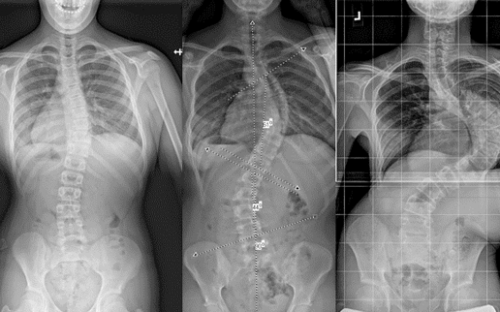

يعاني بعض المراهقين من اعوجاج العمود الفقري، وهو انحناء غير طبيعي للعمود الفقري قد يؤثر على المظهر الخارجي للجسم وثقة الطفل بنفسه. ومن أبرز طرق العلاج غير الجراحي الحزام الطبي، الذي يهدف إلى تثبيت العمود الفقري وتقليل الانحناء مع مرور الوقت. ومع ذلك، تعتمد فعالية الحزام بشكل كبير على دقة توزيع الضغوط داخله، إذ أن الطرق التقليدية غالبًا ما تعتمد على التقدير البصري والخبرة الطبية، مما قد يؤدي أحيانًا إلى نتائج أقل دقة. لذلك، ظهرت تقنيات حديثة تعتمد على المسح ثلاثي الأبعاد لتحسين تصميم الحزام وزيادة فعاليته.

المسح ثلاثي الأبعاد لجسم المريض: حيث يتم عمل مسح كامل للجذع لتحديد مناطق الانحراف بدقة عالية، وهذا يسمح بتخطيط أكثر دقة من الطرق التقليدية.

مقارنة الصورة الأصلية بالنموذج الافتراضي: تُستخدم الخرائط اللونية لتوضيح المناطق التي يتجاوز فيها الانحراف 6 ملم، وبالتالي تحديد نقاط الضغط داخل الحزام بدقة.

1. زاوية كوب (Cobb Angle)

2. تماثل الجذع وشكل الظهر

كانت الفروقات واضحة عند قياس تأثير الحزام على شكل الجسم:

الحزام الجديد حسّن شكل سطح الظهر بنسبة 49.6٪، وهو تحسن ملحوظ.

في المقابل، شهد مستخدمو الحزام التقليدي تدهورًا بنسبة 6.8٪ في شكل الظهر.

التماثل العام للجذع تحسن بنسبة 30٪ مع الحزام الجديد، بينما ازداد سوءًا بنسبة 2.2٪ لدى مستخدمي الحزام التقليدي.

وهذا يدل على أن استخدام القياسات ثلاثية الأبعاد يعزز التماثل العام للجسم بشكل واضح.